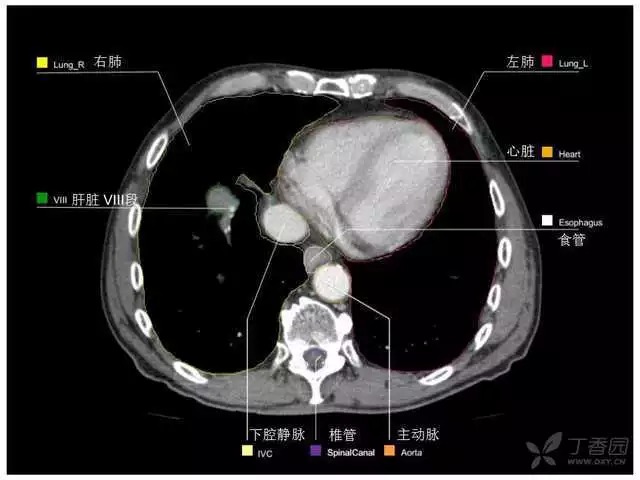

腹部肝脏高清CT断层的图谱

全腹部高清CT图谱,淋巴结彩色图谱,血管解剖图谱大汇总!

肝段,肝内管道的分布规律

美国放射学会ACR官网,对肝脏的区域和节段解剖学概述